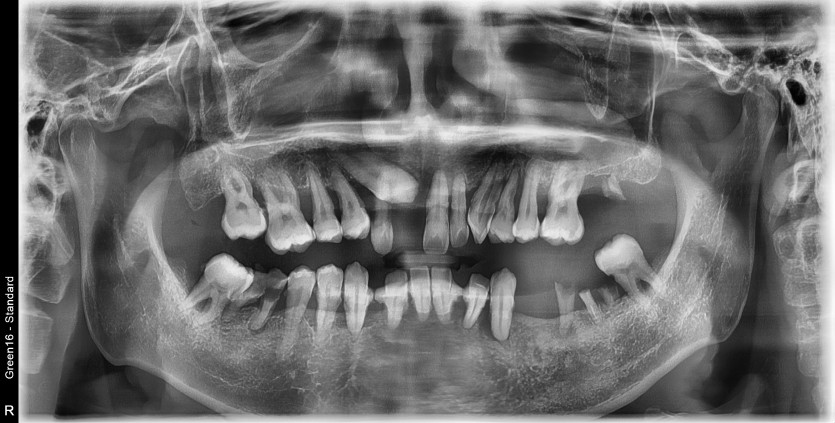

전체 임플란트 증례입니다.

18개의 임플란트로 완성하였습니다.